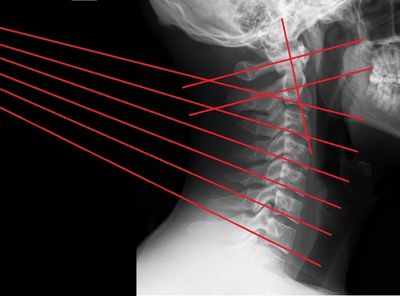

Normal cervical alignment rarely observed in a chiropractic office

X-ray, an important tool to establish the primary spinal problem and rule out pathology